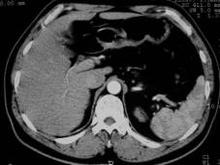

脾-肝综合征是指具有脾大,贫血、肝硬化的一组病征,也称血栓静脉炎性脾大综合征,脾性贫血、充血性脾大综合征、慢性充血性脾肿大,肝脾纤维化、纤维化充血性脾肿大综合征。认为本病是由门静脉反复发生炎症而致门静脉,脾静脉血栓形成及闭塞式或肝硬化引起。